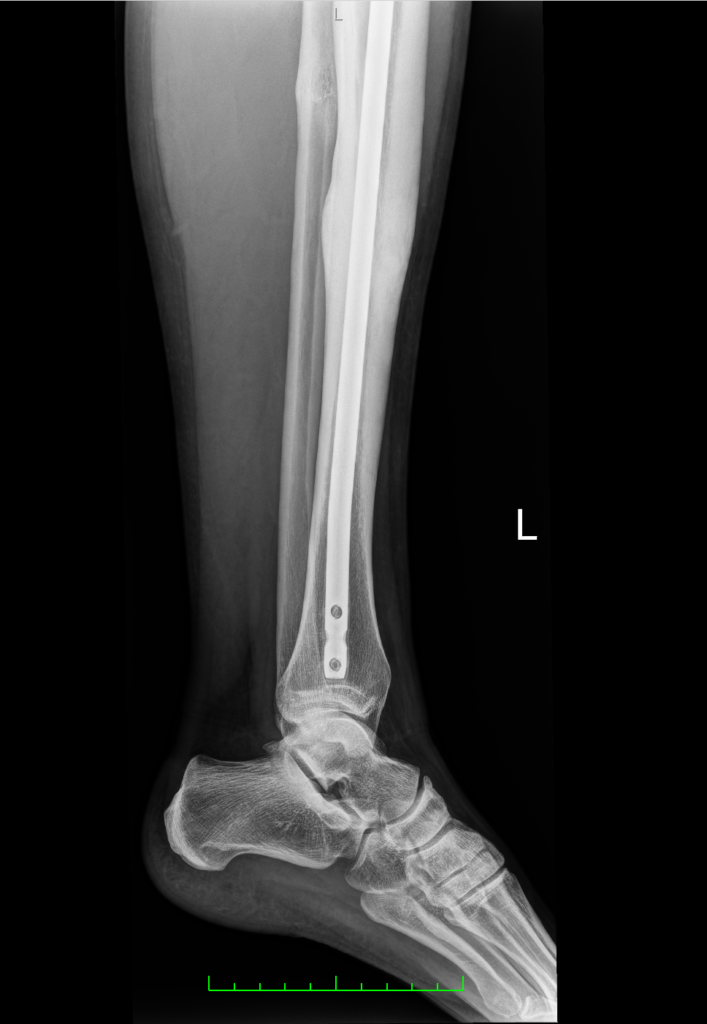

Jeszcze tego samego dnia w Hiszpanii przeszłam operację złamanej piszczeli i strzałki – leczenie z użyciem gwoździa śródszpikowego. Wszystko potoczyło się bardzo szybko. Po ośmiu dniach wróciłam do Polski i niemal prosto z lotniska trafiłam do MotionClinic. Wtedy nie myślałam o sporcie. Chciałam po prostu znowu normalnie stanąć na nodze.